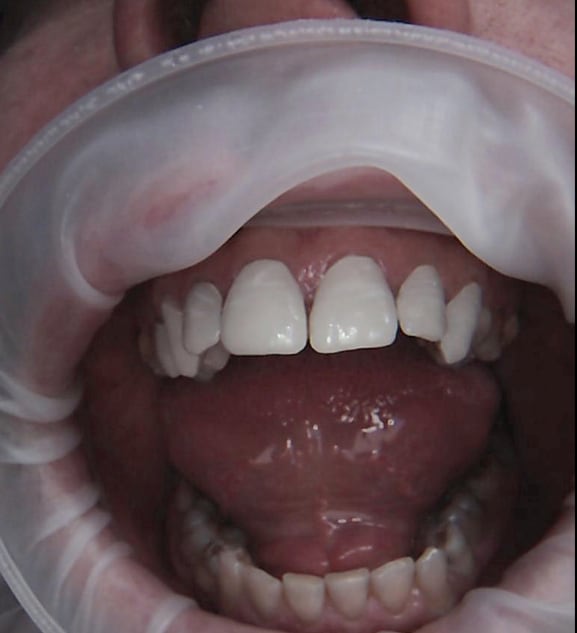

29/04/2016 à 05h32

Ou encore fait dans la matinée

Ps: pas de soucis d'occlusion, juste une propulsion pendant la photo finale. Elle avait dû tenter de retrouver machinalement ce contact bout à bout.